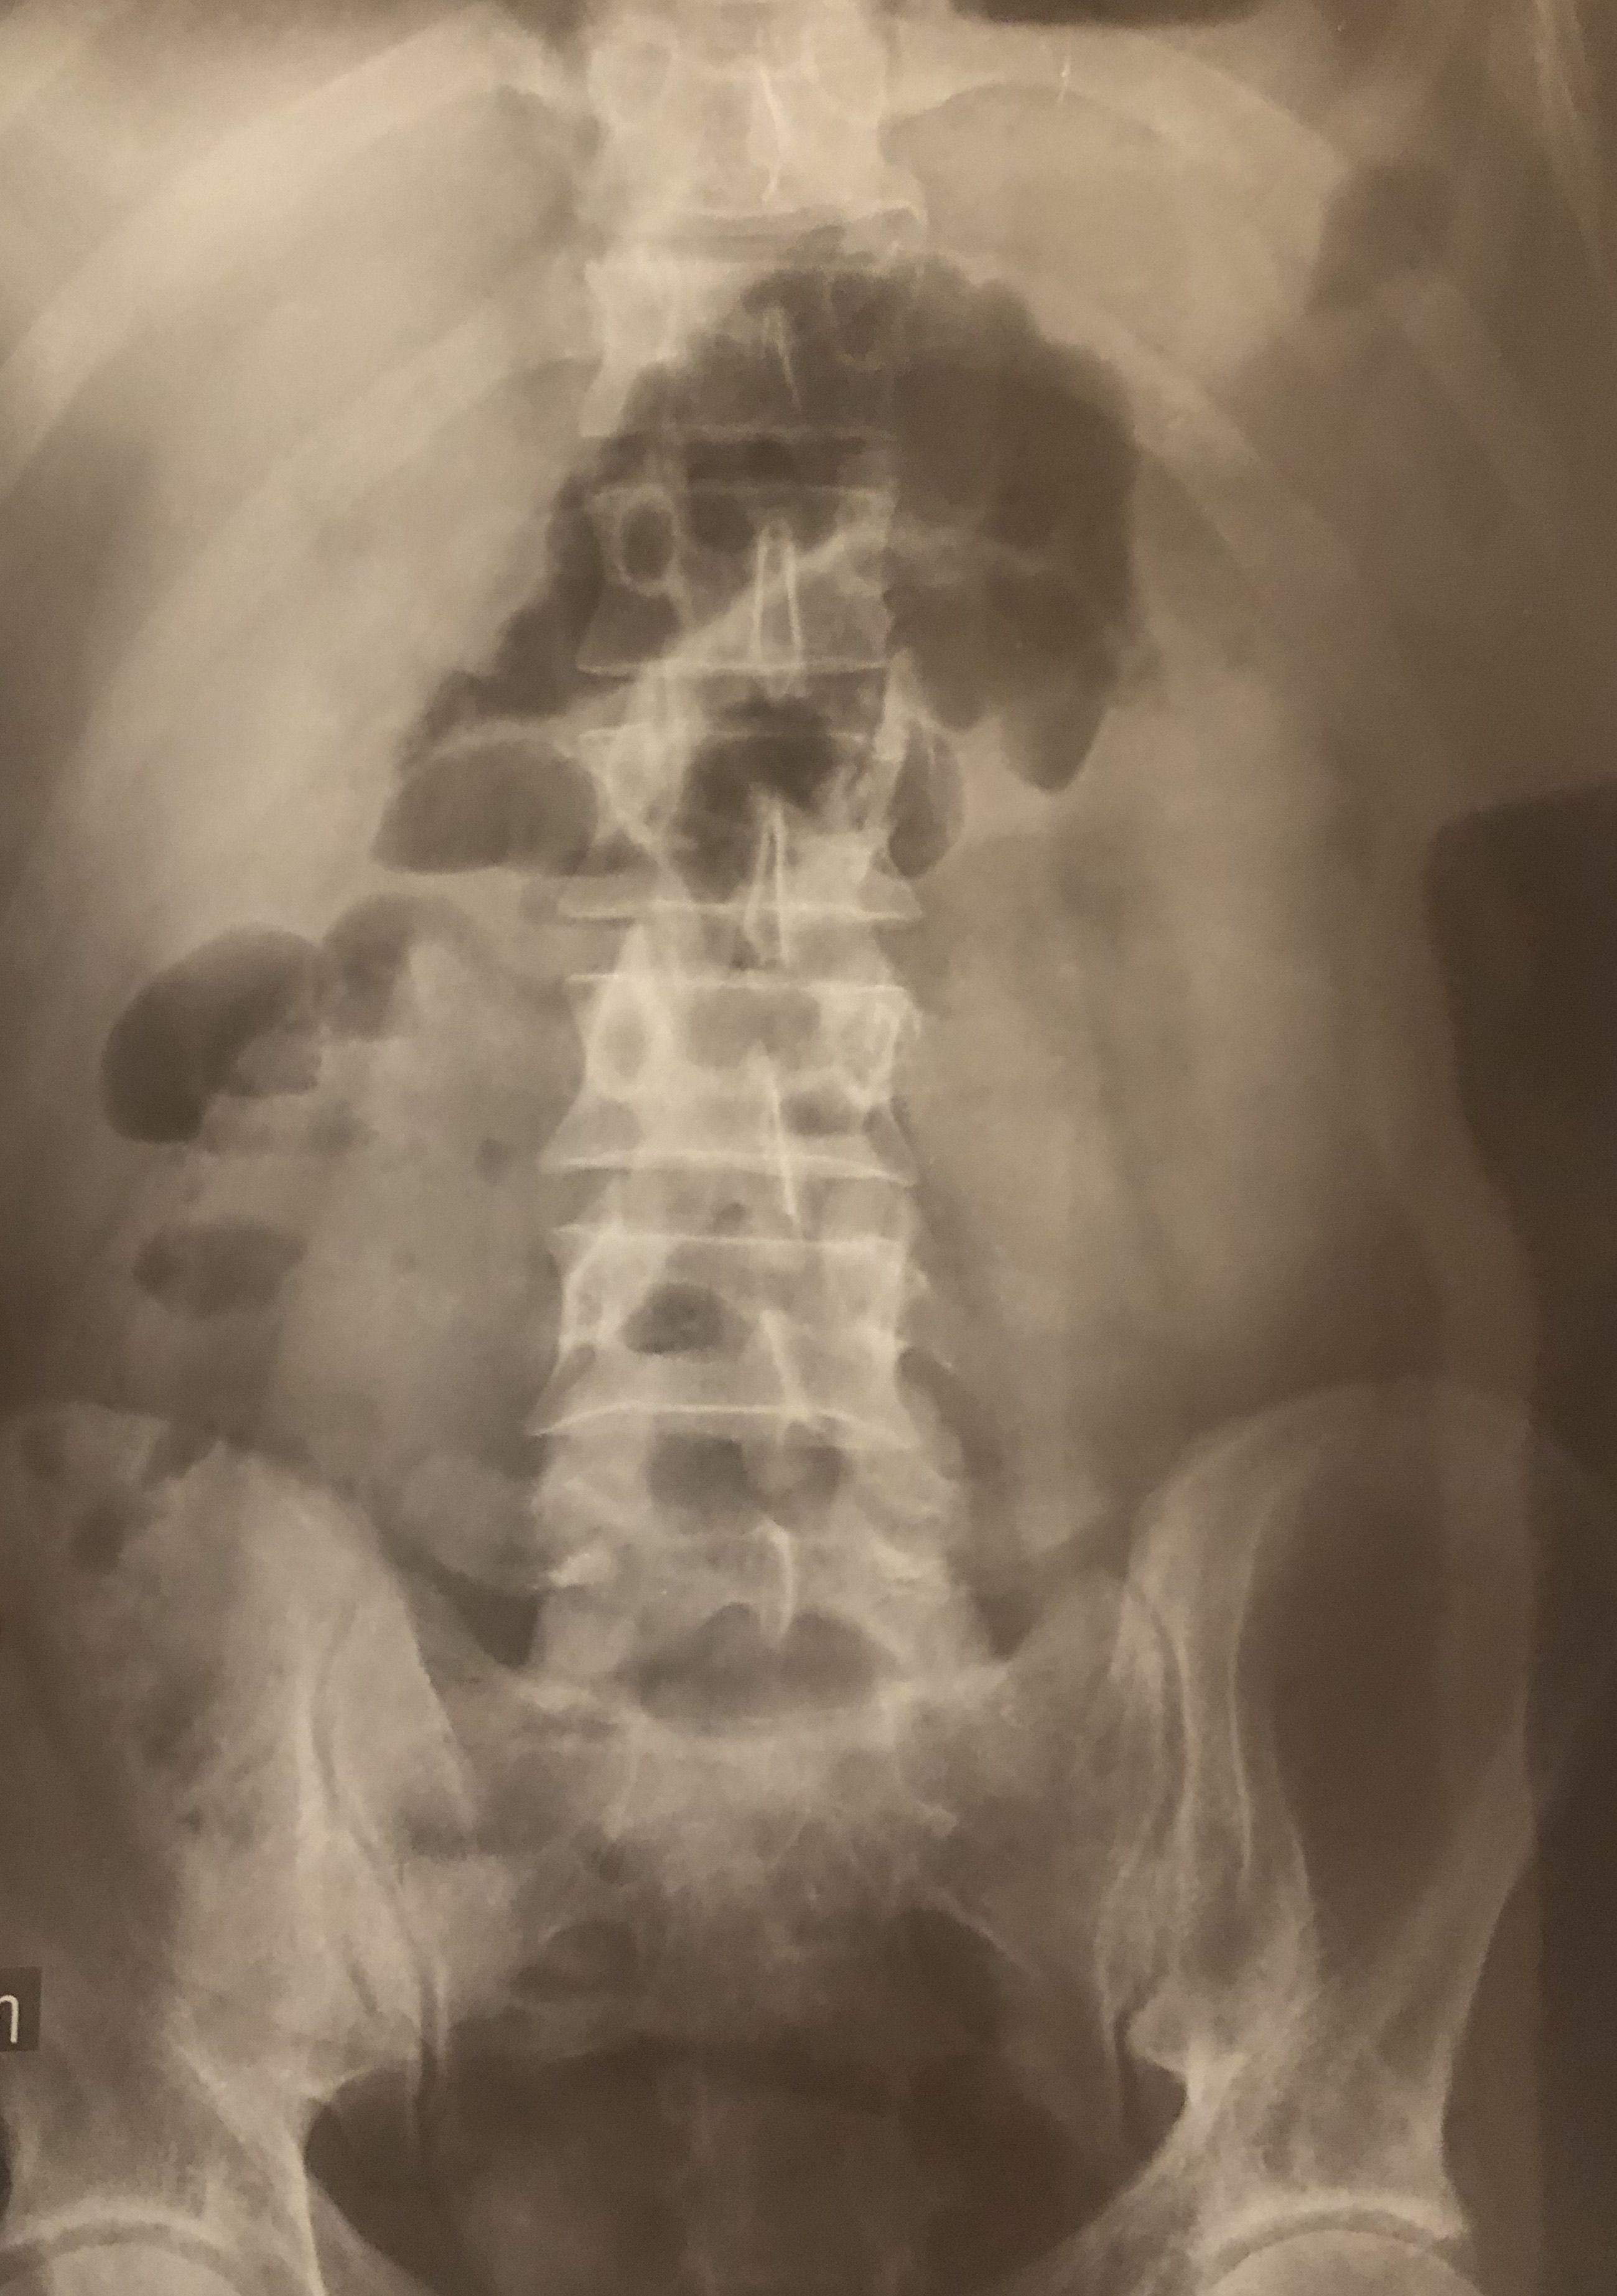

What is your diagnosis?

Bowel obstruction